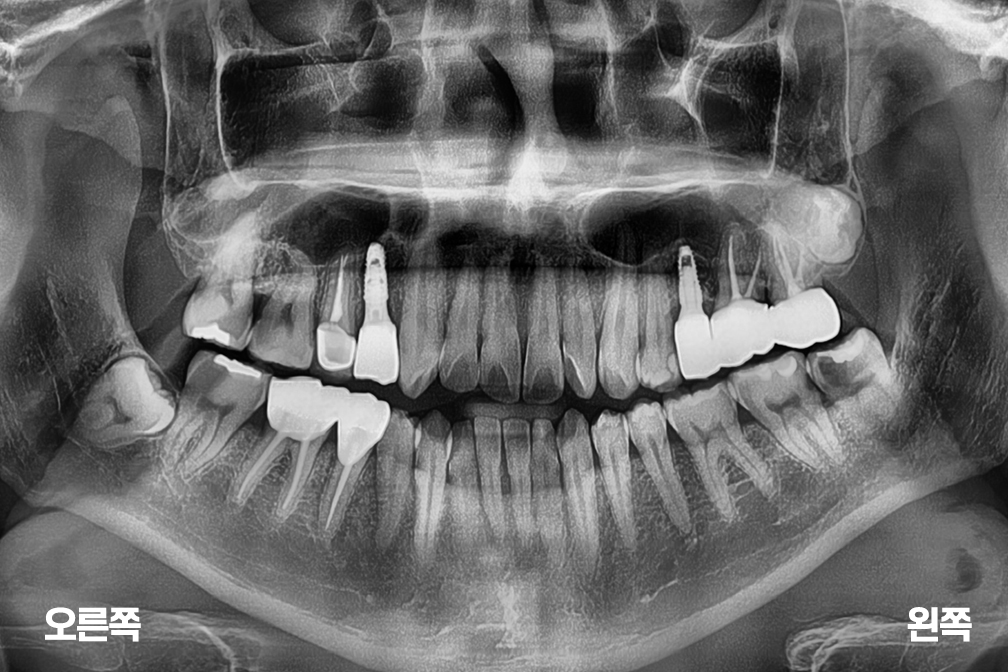

Before 2025년 4월 18일